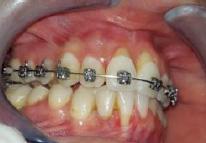

Lâexamen exobuccal Ă©tait sans particularitĂ©s. Lâexamen endobuccal a objectivĂ© une inflammation marginale modĂ©rĂ©e Ă sĂ©vĂšre gĂ©nĂ©ralisĂ©e avec un indice dâOleary Ă 68%, un indice gingival (BoP = Bleeding on Probing) Ă 76%, et un trama occlusal sur 42 (Figure 1). Le bilan parodontal montre des sites avec une profondeur de sondage (PS) de 12mm, et plus de 50% des dents prĂ©sentant une perte dâattache â„ 5mm. Le bilan radiographique a montrĂ© des pertes osseuses terminales, avec un rapport perte osseuse/Ăąge Ă 4,5 (Figure 1)

La thĂ©rapeutique Ă©tiologique a consistĂ© en une Ă©ducation Ă lâhygiĂšne bucco-dentaire, une Ă©limination des facteurs de rĂ©tention de plaque, lâextraction 42+rĂ©section radiculaire et rĂ©alisation dâune contention en fibre de verre avec la couronne ; dâune instrumentation non chirurgicale supra et sous gingivale

par quadrant (3) combinĂ©e Ă une antibiothĂ©rapie (3,4). Une chirurgie avec lambeau dâaccĂšs selon la technique du lambeau avec incision intrasulculaire (open flap) a Ă©tĂ© rĂ©alisĂ©e sur la 46. Une thĂ©rapie parodontale de soutien associĂ©e Ă une phase correctrice a Ă©tĂ© mise en place aprĂšs la thĂ©rapie parodontale active (5). La rĂ©habilitation orale a consistĂ© dans un premier temps Ă rĂ©aliser une correction orthodontique (Figure 2) ; et dans un second temps la conception dâune Ă©pithĂšse gingivale (Figure 3)

AprĂšs 6 mois, pas de profondeurs de poches â„ 6mm, avec un indice de plaque Ă 9% et un indice gingival < 10%. La thĂ©rapeutique non chirurgicale a permis un gain dâattache

stable qui sâest traduit par une diminution des profondeurs de sondage en regard de la 11, 21, et 36 dont le pronostic Ă©tait dĂ©favorable, mais aussi lâapparition dâimportantes rĂ©cessions postthĂ©rapeutique (Figure 4). La chirurgie avec lambeau dâaccĂšs a permis Ă©galement dâamĂ©liorer le niveau osseux de la 46. Le pronostic gĂ©nĂ©ral Ă long terme de la patiente a Ă©tĂ© amĂ©liorĂ©.

La réévaluation Ă 3 mois a montrĂ© une amĂ©lioration de lâĂ©tat parodontal avec plus de 90% de sites prĂ©sentant des PS †4mm (3). LâefficacitĂ© du dĂ©bridement mĂ©canique non chirurgical associĂ© Ă un bon contrĂŽle de plaque individuel dans le traitement des parodontites sĂ©vĂšres a Ă©tĂ© largement documentĂ©e dans plusieurs revues systĂ©matiques (6). Toutefois, la prĂ©sence dâune poche rĂ©siduelle de 6mm avec saignement au sondage sur la 46 reprĂ©sentait un rĂ©sultat incomplet et a nĂ©cessitĂ© dans notre cas un traitement chirurgical par lambeau dâaccĂšs afin dâĂ©viter la progression de la maladie (7).

La rĂ©cession post-thĂ©rapeutique est une observation commune aprĂšs une instrumentation non chirurgicale, particuliĂšrement au niveau des poches profondes et/ou dâun phĂ©notype gingival fin. Notre patiente prĂ©sentait une RT3 sur les incisives centrales rendant son sourire inesthĂ©tique (trou noir). Les restaurations dentaires directes et indirectes et/ou Ă©pithĂšses pouvant ĂȘtre envisagĂ©es (5) ; nous avons optĂ© pour une solution moins invasive en rĂ©alisant une Ă©pithĂšse gingivale. Peu coĂ»teuse et pratique, elle a permis dâoptimiser le rĂ©sultat esthĂ©tique et fonctionnel dans un contexte socio-Ă©conomique limitĂ©.

Figure 4 : (a) Vue clinique Ă 6 mois ; (b) bilan radiographique Ă 3mois (b) ; (c) Retro alvĂ©olaire sur la 46 avant et aprĂšs lambeau dâassainissement